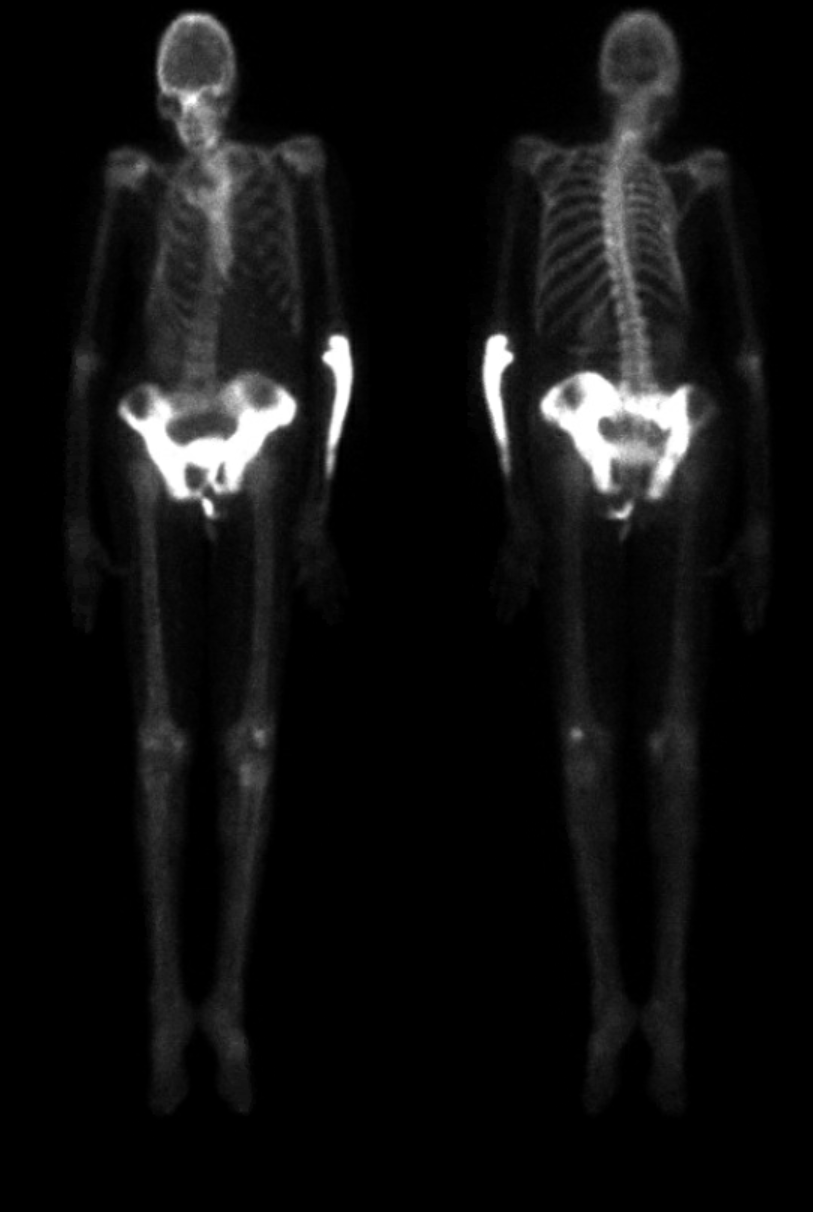

Paget's Disease On Bone Scan . It is the second most frequently diagnosed. In a bone scan, radioactive material is injected into your body. Paget disease is a skeletal growth disorder in which abnormalities such as unusual bone growth can occur in several multifactorial ways. Providers sometimes use bone scans to see which bone(s) are affected by paget’s disease and how mild or severe it is. Paget disease is the second most common bone disease after osteoporosis that affects elderly persons in the united states. We revisit paget disease of bone and present the gamut of imaging. The two main clinical manifestations of paget disease are pain due to the pagetic lesion in bone itself or from secondary consequences of. This material travels to the spots on your bones most affected,. Paget disease of bone is a benign skeletal disorder characterized by focal areas of increased bone resorption and disorganized bone formation. 1 these focal lesions, called.

Paget’s disease. Three phase bone scan (a and b) in a 61yearold... Download Scientific Diagram Paget's Disease On Bone Scan Paget disease of bone is a benign skeletal disorder characterized by focal areas of increased bone resorption and disorganized bone formation. Providers sometimes use bone scans to see which bone(s) are affected by paget’s disease and how mild or severe it is. Paget disease is a skeletal growth disorder in which abnormalities such as unusual bone growth can occur in. Paget's Disease On Bone Scan.